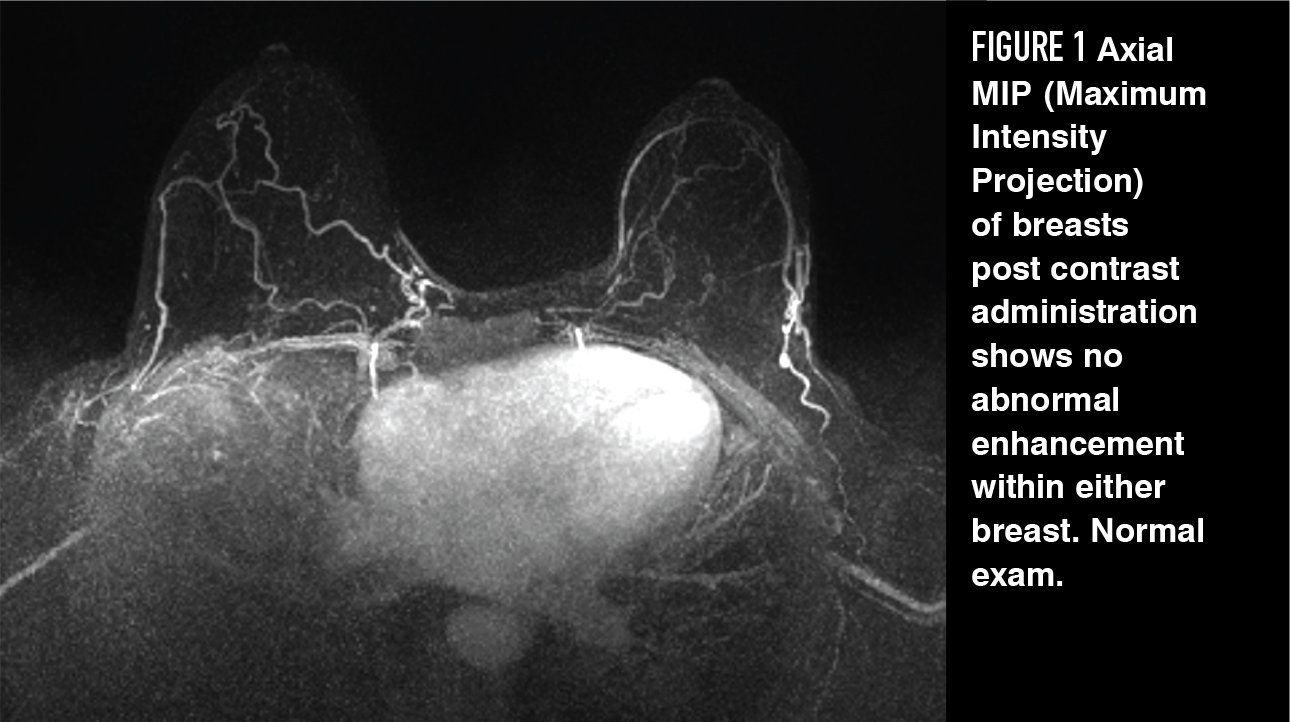

Figure 2

In observational studies, adding contrast-enhanced MRI to annual mammography in BRCA mutation carriers significantly improved detection of early, treatable breast cancers with a combined sensitivity of 94% compared to 39% with mammography alone.18,22,23 MRI provides a functional assessment of breast tissue. Contrast- enhanced MRI can detect microvascular changes and peritumoral inflammation as the contrast accumulates rapidly, and is then washed out rapidly, in more vascular tumors compared to benign breast tissue. Consequently, annual contrast-based MRI has been incorporated into breast cancer surveillance guidelines for women at the highest risk of breast cancer.24